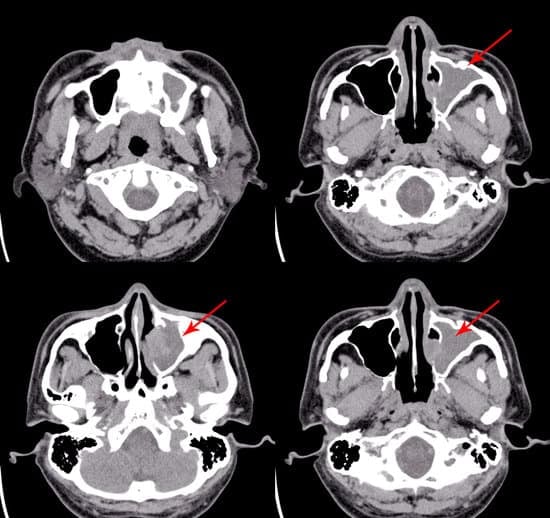

영상 검사: CT 스캔으로 만성 부비동염 및 복잡한 부비동 문제 진단

CT 스캔(Computed Tomography)은 만성 부비동염 및 복잡한 부비동 문제를 정밀하게 확인하는 데 사용되는 영상 검사 방법입니다. 특히, 단순한 신체검사나 내시경으로 파악하기 어려운 부비동 내부 상태를 상세히 진단할 수 있습니다.

4. CT 스캔으로 확인 가능한 사항

부비동 내 염증 및 농:

점막 두꺼움, 부비동에 고인 농 또는 액체 확인.

안와 감염, 농양, 또는 뇌와 연결된 부위의 염증 여부.